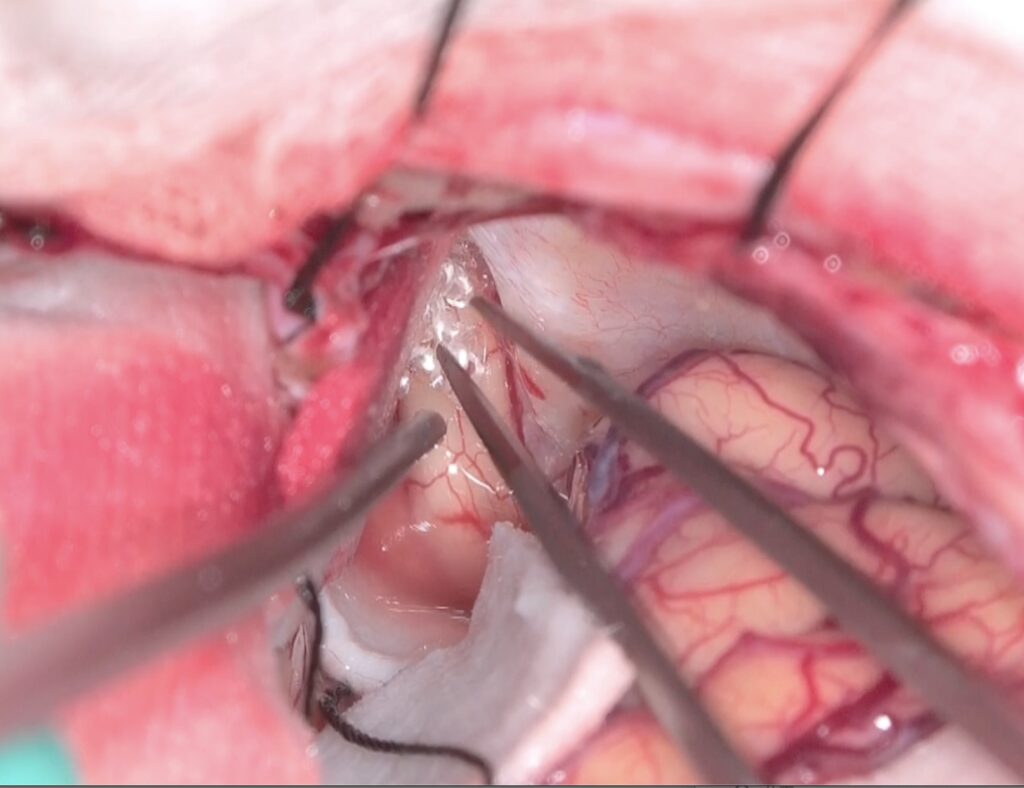

両側のGyrus rectusを剥離、前頭底にいたり、視神経と下垂体茎が見えます。

Trans-lamina terminalis approach、何度もやった古典的なアプローチです。A2と伴奏し縦走する視床下部動脈を温存して、その間隙から腫瘍を減圧していきます。